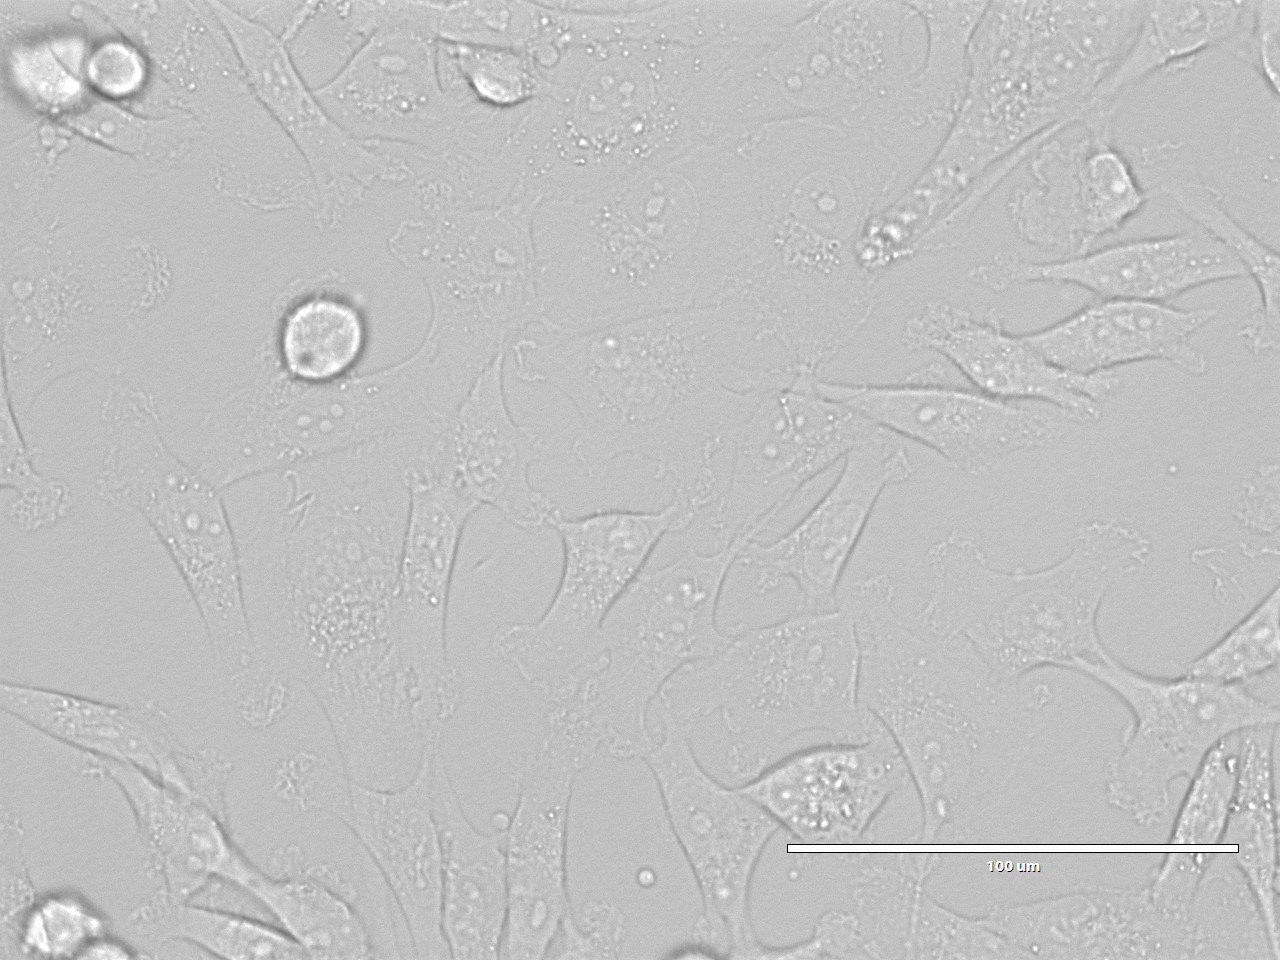

MDA-MB-231(人乳腺癌细胞)

MDA-MB-231(人乳腺癌细胞)MDA-MB-231是从一名51岁的白人女性乳腺癌患者的胸水中分离建立的。该细胞表达表皮生长因子EGF受体、TGF-α受体和WNT7B癌基因。常用于肿瘤转移和侵袭性的研究。

细胞形态 上皮细胞样

生长特性 贴壁细胞